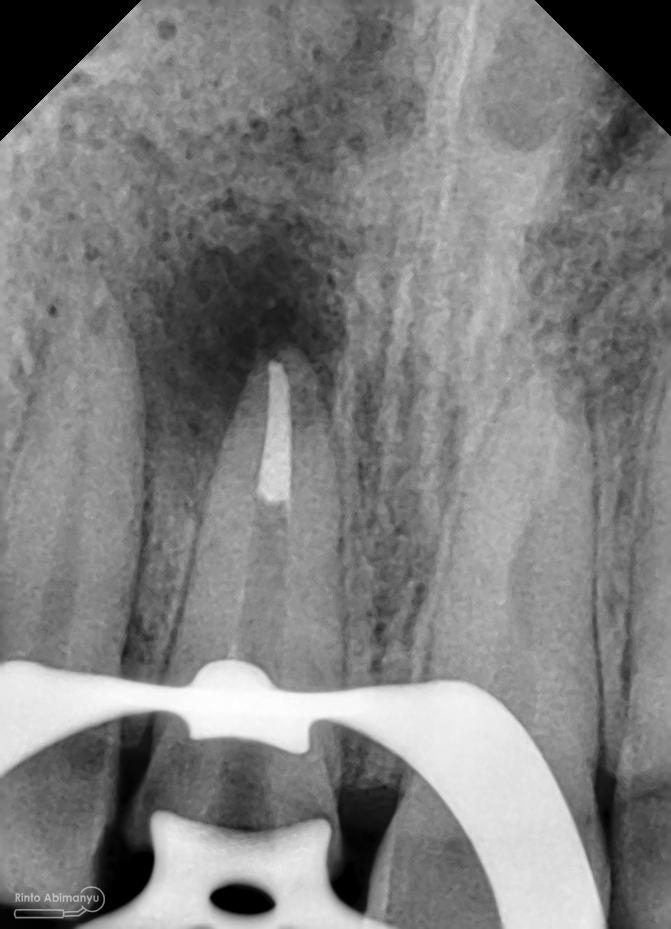

Foto radiografis trial guttap

Dari ronsen terlihat guttap sudah pas dan langsung hari itu juga saya lakukan pengisian saluran akar kemudia pasien pulang…. Pada saat selesai pengisian tidak saya lakukan ronsen lagi karena saya merencanakan ronsen evaluasi pengisiannya sekalian foto ronsen saat pengepasan guttap pada gigi 22 saja biar efektif…

Foto radiografis trial guttap gigi 22

Nah dari foto ronsen ini juga saya melakukan evaluasi hasil pengisian pada gigi 11 21 nya… alhamdulillah pengisian yang kemarin terlihat sepanjang kerja dan padat serta rapat… Pada gigi 22 nya pun pengepasan guttap terlihat sudah sepanjang kerja…

Foto radiografis selesai perawatan saluran akar pada semua gigi

Foto radiografis akhir

Dari foto ronsen terlihat gambaran yang “indah” dari mulai pengisian saluran akar yang rapat dan padat serta gambaran sementasi mahkota yang terlihat homogen….